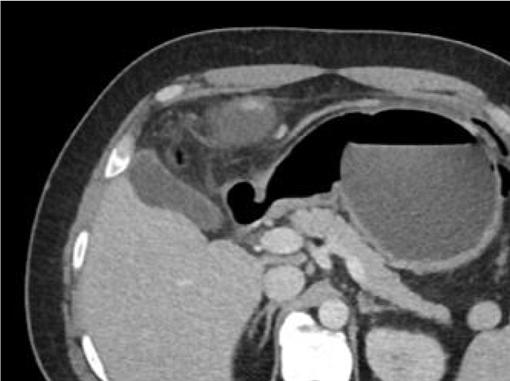

A31-year-oldobese,Hispanicmalepresentedtothe emergencydepartmentwithprogressivelyworseningleft upperquadrantabdominalpainfor fivedays.Thepainwas describedascramping,intermittent,andexacerbatedby bendingforward.Hedeniedpastmedicalhistory. Severaldayspriortopresentationthepatienthadbeen evaluatedbyhisprimarycarephysician.Hewasdiagnosed withmusculoskeletalpainandprescribedcyclobenzaprine. Sincetheevaluationbytheprimarycarephysician,thepain hadincreasedinfrequencyandintensity.Thepatientdenied anynausea,vomiting,fevers,diarrhea,orhematochezia.He did,however,reportintentionalweightlossof15kilograms. Tenweeksprior,thepatienthadingestedanIGB(Allurion,

formerlyknownasElipse),forweight-losspurposesunder thecareofaphysicianinJuárez,Mexico.

Oninitialevaluation,vitalsignswerenormalexceptfor sinustachycardiaat105beatsperminute.Hewasinmild distresswithmoderatetendernesstopalpationintheleftupper quadrant.Therewasnoguarding,rebound,orrigidity. Laboratoryevaluationshowedawhitebloodcellcountof 21.7 × 103 cellspercubicmillimeter(mm3)(referencerange 4.5 11 × 103 cells/mm3)withaneutrophilpredominanceof 18.9 × 103 cells/mm3 (2 7.8 × 103 cells/mm3)andanelevated bloodureanitrogenat25milligrams(mg)/deciliter(dL) (9–20mg/dL).Thepatient’selectrolytes,liverfunction tests,andserumcreatininewerewithinnormallimits. Acomputedtomography(CT)oftheabdomenandpelviswith intravenouscontrastwasorderedtoassessforbowel obstruction,perforation,andballoonintegrity.TheCT indicatedintraluminalgastricballoonwithanteriorgastricwall perforationwithoutevidenceofintestinalpathology(Image).

GeneralsurgerywasconsultedandobtainedaCT abdomenandpelviswithoralcontrast,whichdirectly showedextravasationintotheperitonealcavity.Thepatient wasemergentlytakentotheoperatingroomforan exploratorylaparotomy,abdominalwashout,removalofthe IGB,andgastricperforationrepair.Hewasstartedon piperacillin/tazobactamand fluconazoleforpurulent peritonitis.Afteranovernightstayinthesurgicalintensive careunit,hewastransferredtothesurgical floorwherehe remainedforthefollowing10days.Onday5,afollow-up uppergastrointestinalserieswithgastrografinwasobtained, andnocontrastextravasationwasnoted.Thepatient’sdiet wasadvanced,andhewasdischargedonpostoperativeday 10withamoxicillin-clavulanatefor10days.Forty-twodays afterdischargethepatientwasnotedtoberecoveringwellon afollowupvisit.